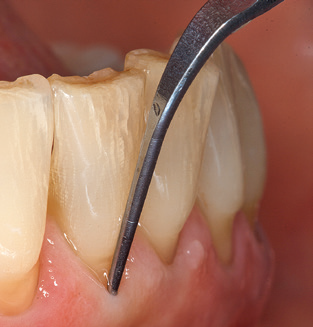

Following machine cleaning of the tooth and implant surfaces, the surfaces of the natural teeth are cleaned manually using standard hand instruments. When performing manual cleaning, particular attention must be given to maintaining the correct angle of application, appropriate sharpness, good support and working with the curette from apical to coronal. Either titanium or carbon curettes should be used for post-cleaning of the implant structures (Fig. 8). In addition to the use of ultrasonic devices, power jet devices can also be used in conservative dentistry. However, it must be taken into consideration that these procedures are not suitable for removing hard deposits and thus they cannot replace the use of hand instruments and ultrasonic instruments completely. In all cases, cleaning is followed by mechanical polishing of the accessible tooth and implant surfaces with polishing cups and polishing compounds (Fig. 9).